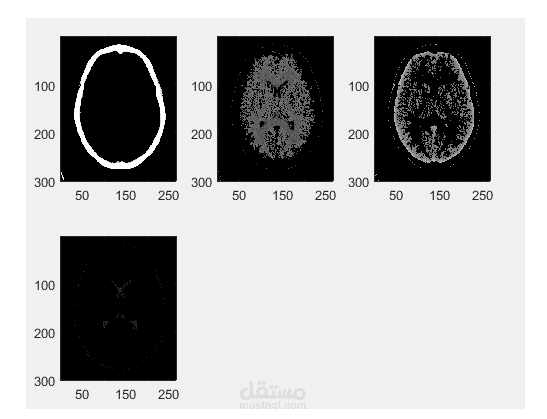

image segmentation matlab